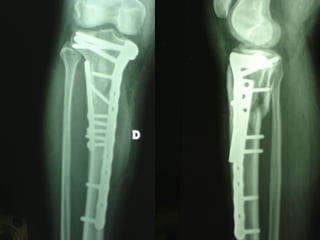

Dal Gennaio 2000 al Febbraio 2006 abbiamo trattato 167 fratture chiuse  con placca percutanea  in 164 pazienti :  27 lesioni diafisarie di gamba, 12 piloni tibiali ,  11 fratture prossimali di tibia, 36 fratture sovracondiloidee di femore, 17 fratture diafisarie di femore, 43 fratture metaepifisarie prossimali di omero, 21 diafisarie d’omero.  156 guarigioni 8 fallimenti

Dal Giugno 2002 al Dicembre 2004 abbiamo trattato 5 fratture esposte: 3 di tibia e 2 di ulna 5 guarigioni

I buoni risultati ottenuti dipendono da 5 punti fondamentali:   una accurata riduzione percutanea della frattura  precise vie di accesso  l’utilizzo della placca che consenta il più lungo braccio di leva possibile il pretensionamento della placca  una sintesi con un ridotto numero di viti

Precise vie di accesso

Placche lunghe e pretensionate

Placche lunghe e pretensionate Sintesi con un ridotto numero di viti

Fratture  esposte